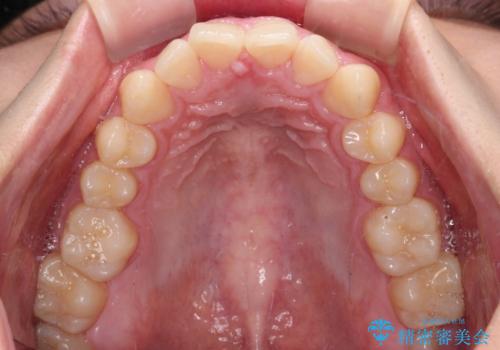

- 上下前歯のデコボコと深い咬み合わせを気にして来院された患者様です。

下顎前歯が一本欠損しており、下顎の歯列が小さいため、ディープバイトになりやすい状態でした。

傾斜しいている大臼歯を立ち上げながら、下顎歯列を上顎に対して前方位となるように工夫し、デコボコを解消した上でディープバイトも改善することができました。